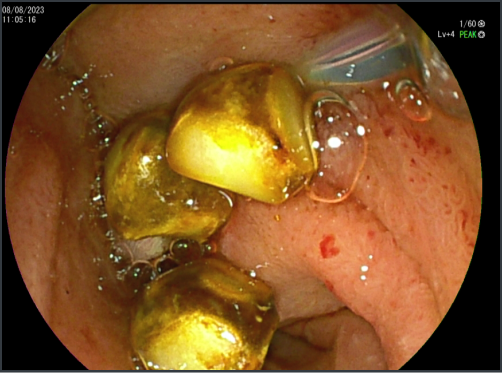

Biliar - CPRE

Extracción de Cálculos Biliares

Extracción Cálculos Pancreáticos